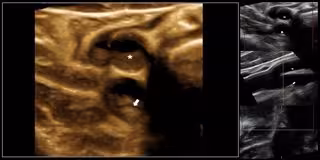

La ecografía tridimensional vascular es una técnica de imagen "factible, reproducible y novedosa" para cuantificar de forma precoz la carga ateroesclerótica global que ayuda a identificar el riesgo cardiovascular, y ahora se ha demostrado que es "más precisa" que las técnicas bidimensionales a la hora de estimar esta carga, según el estudio 'Progression of Early Subclinical Atherosclerosis' (PESA) CNIC-Santander, que se ha publicado en 'The Journal of the American College of Cardiology'.

"Este nuevo método es válido para obtener una imagen de la carga de aterosclerosis periférica (carótidas y femorales) desde las etapas tempranas a las más avanzadas de la enfermedad, pudiéndose aplicar en la identificación de aquellos individuos con un mayor riesgo y así ofrecer tratamientos más dirigidos y monitorizarlos", ha explicado el director general del Centro Nacional de Investigaciones Cardiovasculares Carlos III (CNIC) y autor principal de la investigación, Valentín Fuster.

Para el estudio PESA, los investigadores del CNIC exploraron las regiones más significativas desde el punto de vista de la aterosclerosis de las arterias carótidas y femorales (un segmento arterial de unos 6cm de longitud centrado en el bulbo carotideo y en la bifurcación femoral) de forma bilateral y de manera tridimensional. En este sentido, los resultados de la investigación mostraron que la carga global de aterosclerosis en las personas analizadas (edad media 45 años) es dos veces más alta en hombres que en mujeres (63,4 milímetros cúbicos frente a 25,7), y también más elevada en las arterias femorales que en otros territorios vasculares, además de que aumenta con la edad.

No obstante, la aplicación técnica de la ecografía tridimensional vascular se encuentra todavía en fase de investigación y "se necesitan más estudios para evaluar la utilidad de este nuevo método que lo comparen con los métodos tradicionales", según el doctor Fuster. Sin embargo, ya hay una serie de áreas en las que ha demostrado ser clínicamente prometedora, incluyendo la cuantificación del volumen de la placa aterosclerótica.